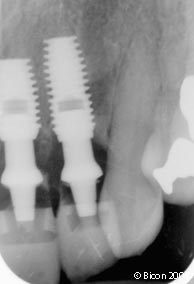

2. | 种植体植入15周后的X光片显示已结合的种植体。 |

26. | 一体化基台冠的术后X光片。 |